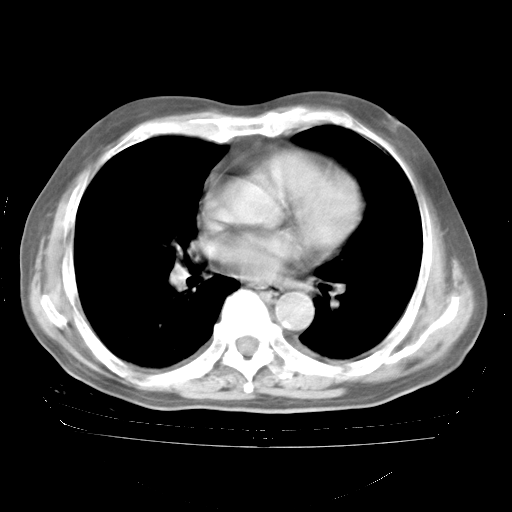

4月28日肺部CT——再次出现类似去年5月9日——磨玻璃样、间有“粟粒样”改变。